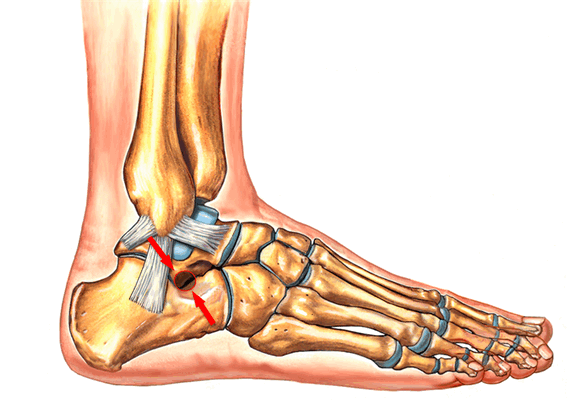

Рентгенография используется для определения угла между линиями, проведёнными между первой плюсневой костью и проксимальной фалангой первого пальца. Если угол больше 15°, подтверждает диагноз hallux valgus. Если угол составляет 45-50° — консервативное лечение не показано. Также должны быть определены степень смещения сесамовидных костей и уровень остеоартрита первого плюсне-фалангового сустава.

Угол, образованный линиями, одна из которых проходит вдоль проксимальной фаланги, а другая вдоль плюсневой кости, известен как угол отклонения большого пальца. Значение меньше 15° градусов считается нормальным. Угол более 20° и более указывает на патологию. Тяжелый случай — это когда угол составляет 45-50°

Тестирование пациента должно осуществляться два раза: в положении сидя и стоя. В положении стоя деформация стопы наиболее выражена. Во время исследования также необходимо обратить внимание на плоскостопие и степень натяжения ахиллова сухожилия, высоту продольного свода и положение большого пальца по отношению к остальным.

Если неоперативное лечение не помогло, необходимо рассмотреть вопрос о хирургическом лечении (уровень доказательности: 4). Перед выполнением операции необходимо определить степень тяжести hallux valgus. Для этого следует выполнить рентгенографию стоп в положении стоя.